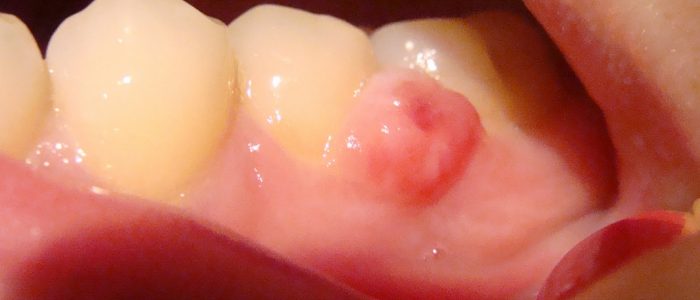

Пиогенная гранулема

Состоит из соединительной и слизистой тканей ротовой полости. Основная причина возникновения — нарушение целостности тканей в результате механических травм и повреждений. Образование увеличивается в размерах (до 20 мм), кровоточит и болит при раздражении. В этих случая нельзя самому пытаться справиться с проблемой, так как высокий риск развития осложнений.

Образования эпулисы отличаются стремительным ростом и кровотечениями.

Образования эпулисы

Доброкачественное новообразование, основное место расположения — десна. Эмпулисы прорастают из глубинных слоев десен, клеток периодонта, надкостницы. Чаще всего локализуются на деснах между передними зубами. Различают фиброзные, гигантоклеточные, ангиоматозые эмпулисы. При стечении обстоятельств эимулисы перерастают в раковое новообразование, поэтому если нарост стремительно увеличивается и кровоточит, стоит посетить врача.